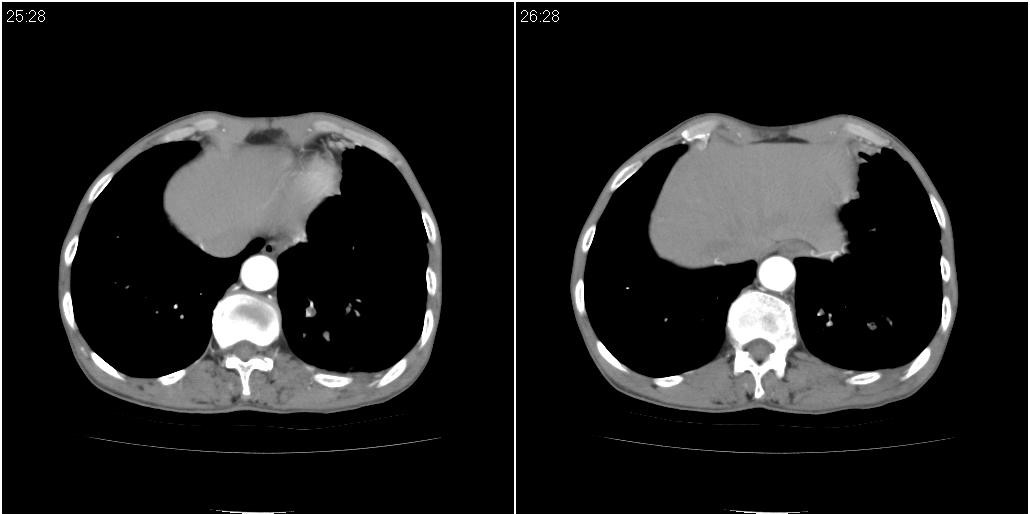

标题: CT25416:男性,70岁。胸片发现右下肺斑片状阴影

以下是ct检查的情况:

标题: ct增强:

考虑右肺下叶炎症可能性大?未除占位,建议增强。右下肺肺不张

1)右肺中叶慢性炎症并支气管扩张,节段性肺不张。2)两肺下叶支气管扩张。